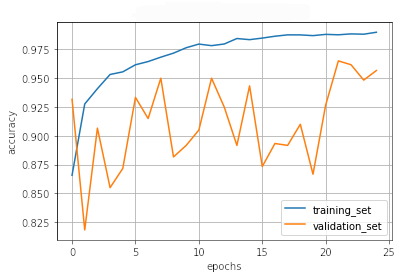

III.2 Classification results

The training procedure in all scenarios has converged. Looking at the evolution of training and validation accuracy (Fig. 11a) indicates that a larger validation dataset would be beneficial. To stabilise the classifier training a procedure of multiple training runs to select the best model is used (Materials and methods). Resulting classifiers are able to discriminate between classes with good precision, for example, see the confusion matrix of the best overall model presented in Fig. 11b. It can also be seen that for the normal class, the rate of misclassified images as COVID-19 ones is higher than for other classes. This effect is present for all models although smaller for the ones based on the EfficientNet-B0 architecture. In addition, the EfficientNet-B0 variants excel if the correct classification of viral pneumonia class images with the smallest rate of errors. However, the EfficientNet-B0 GAN augmentation scenario shows increased misclassification of healthy images which leads to a poor performance. The evolution of the training accuracy as well as confusion matrices for all models are summarised at the end of this section.

Training results for the two architectures are summarised in Figs. 13, 14, 15, 16, and Table 3. For each architecture four scenarios are considered as described in Training process part of the Materials and methods Section.